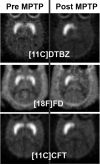

- Perlmutter JS, Tempel LW, Black KJ, et al. MPTP induces dystonia and parkinsonism: Clues to the pathophysiology of dystonia. Neurology. 1997;49:1432–1438. - PubMed

- Nagai Y, Obayashi S, Ando K, et al. Progressive changes of pre- and post-synaptic dopaminergic biomarkers in conscious MPTP-treated cynomolgus monkeys measured by positron emission tomography. Synapse. 2007;61:809–819. - PubMed